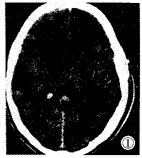

颅脑CT平扫:右侧颞顶叶见5cm×5cm×6cm圆形混杂密度影,周边轻 度水肿,左额叶见1cm×1cm×1cm圆形稍高密度影,周边轻度水肿(图1,2)。

图1,2 平扫右颞顶叶见5cm×5cm×6cm圆形混杂密度影 ,周边轻度水肿;左额叶见1cm×1cm×1cm圆形稍高密度影,周边轻度水肿